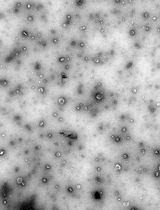

Lipid nanoparticles (LNPs) are powerful carriers for nucleic acid delivery, but plasmid DNA-loaded LNPs (pDNA-LNPs) have been limited by inflammation and toxicity. We showed that standard pDNA-LNPs activate the cGAS–STING pathway, leading to severe immune responses and mortality in mice. To overcome this, we co-loaded nitro-oleic acid (NOA), an endogenous STING inhibitor, into pDNA-LNPs. NOA-pDNA-LNPs mitigated inflammation, enabled safe in vivo delivery, and supported sustained gene expression for months. Here, we present a detailed protocol for producing and characterizing NOA-pDNA-LNPs to facilitate safer, long-term gene delivery applications.

Lipid nanoparticle (LNP) production process. 1. Prepare lipid and DNA mixes in separate 2 mL Eppendorf tubes. 2. Mix the two phases using either a microfluidic chip or a vortex mixer. 3. Dialyze the formed LNPs against 1× PBS, pH 7.4, for 2 h to remove remaining ethanol and adjust pH. 4. Validate LNP quality before use or storage.